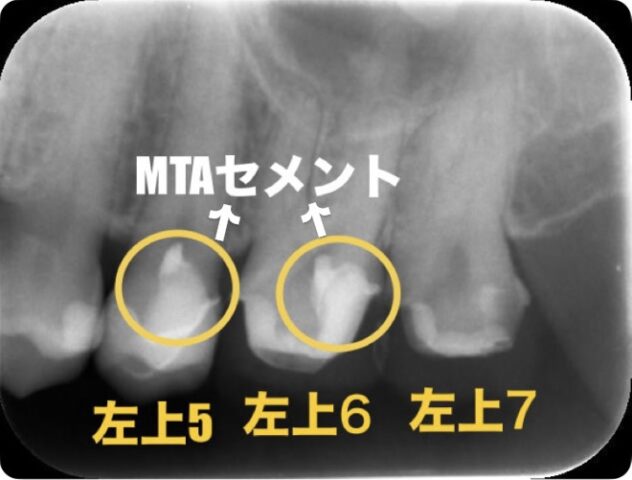

動画で紹介したのは5番目のみですが、6番目は同じように歯髄温存療法を行うほどに感染してしまっていました。7番目は感染は多く残っていましたが、神経までは広がっていませんでした。

治療後のレントゲン写真がこちらです

この後は経過観察を行い、神経が生きていることを確認した後に、最終の補綴を入れました。

今回の症例はレントゲン写真を見てもわかるくらい大きく感染してしまっていました、